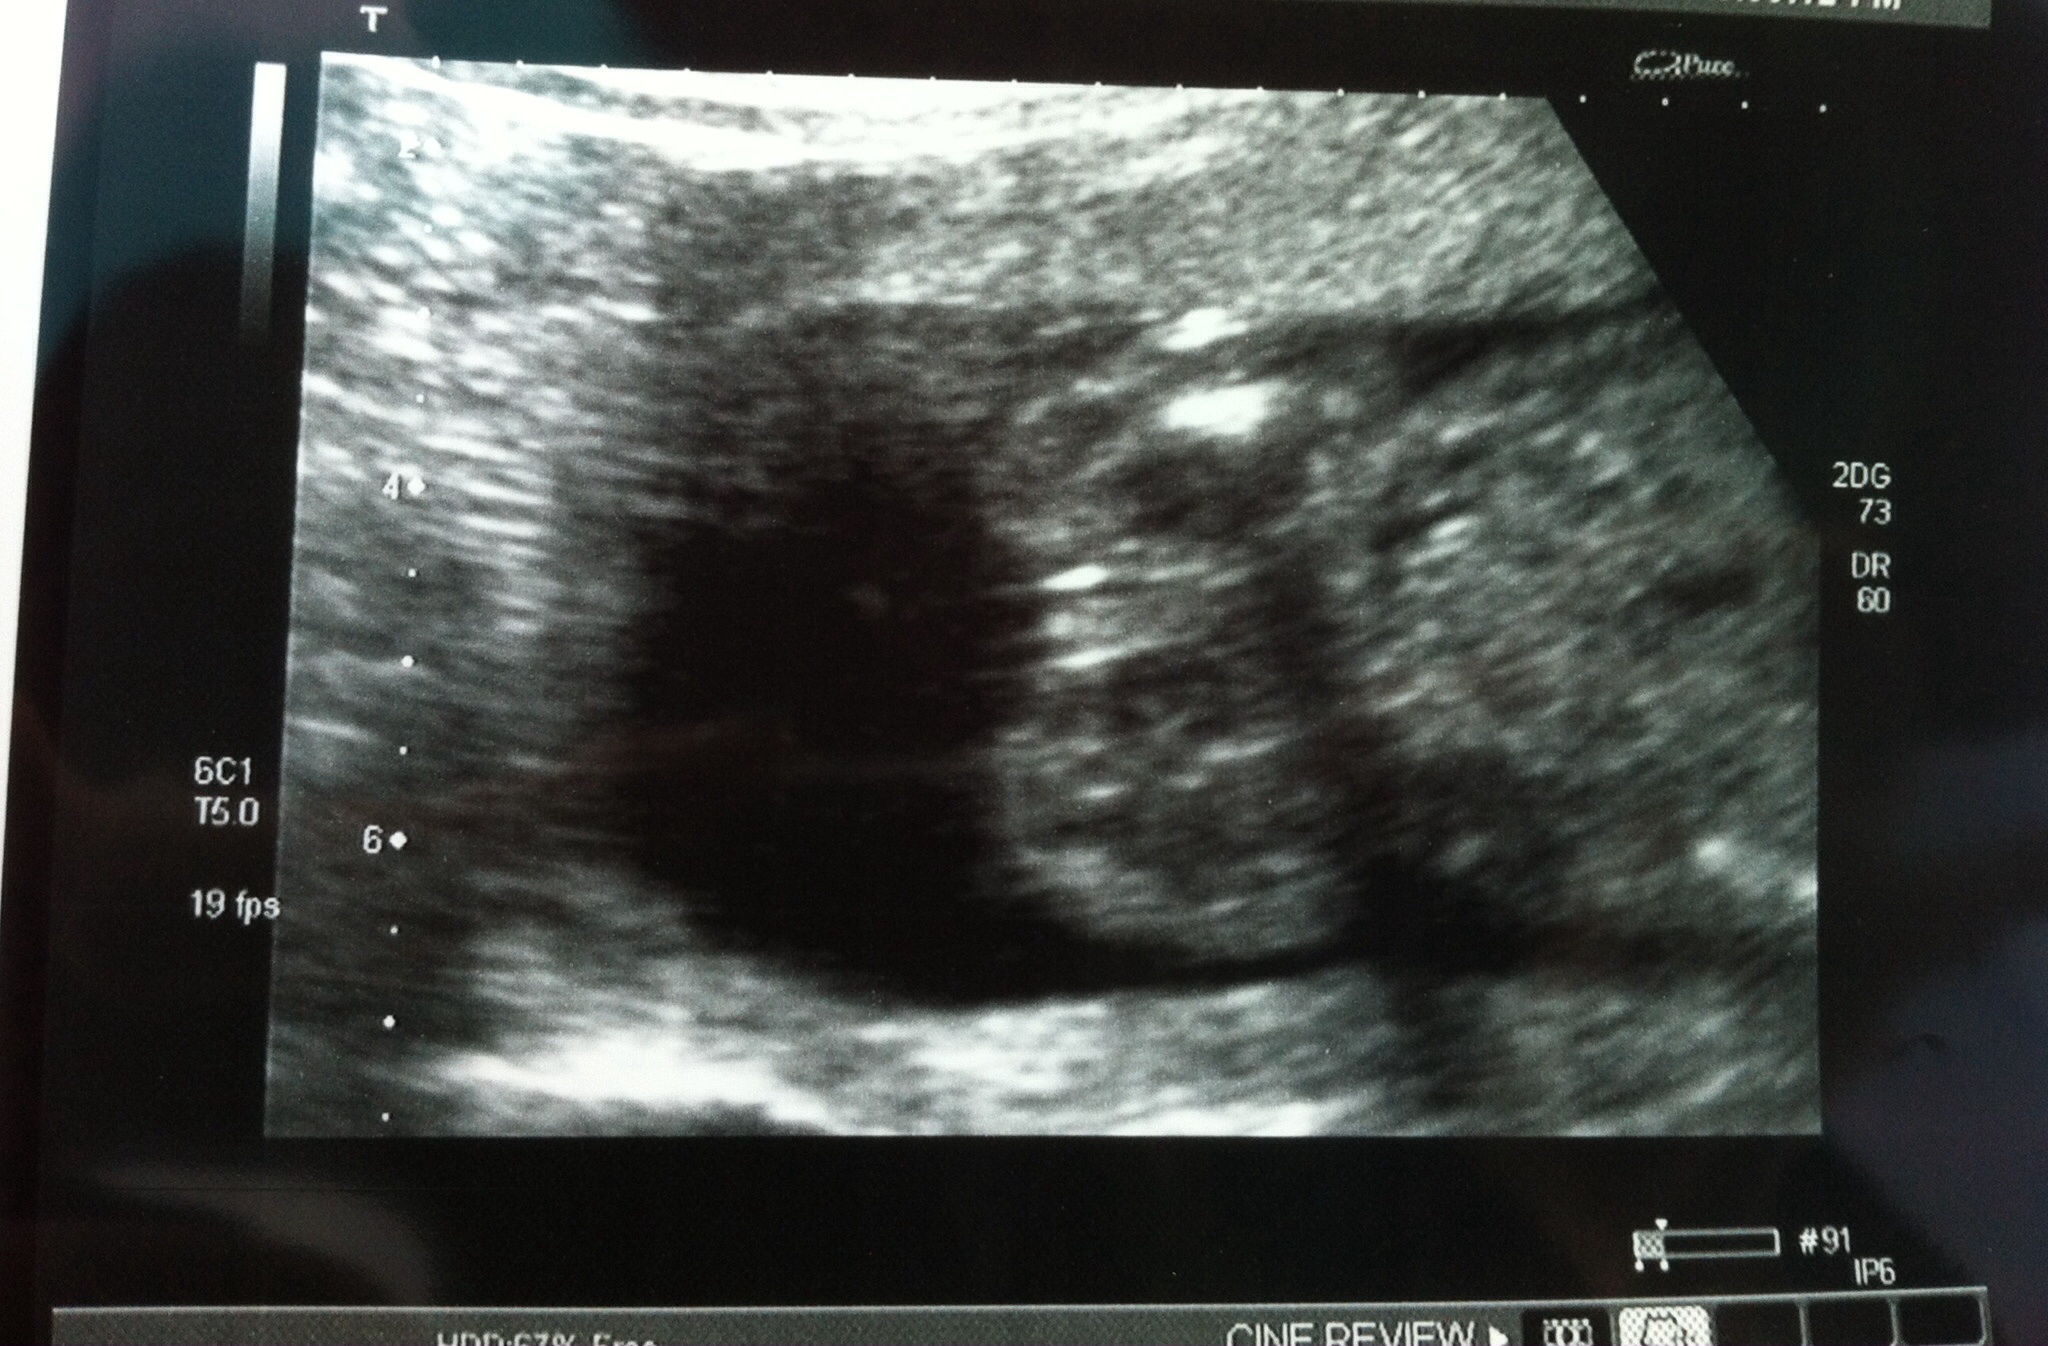

19 week ultrasound - can you confirm this is a girl. Thanks for your help all!!!Attachment 23228

That's a little girl :)

Definitely girly, congrats!

That is a girl no doubt!!!

100% girl!